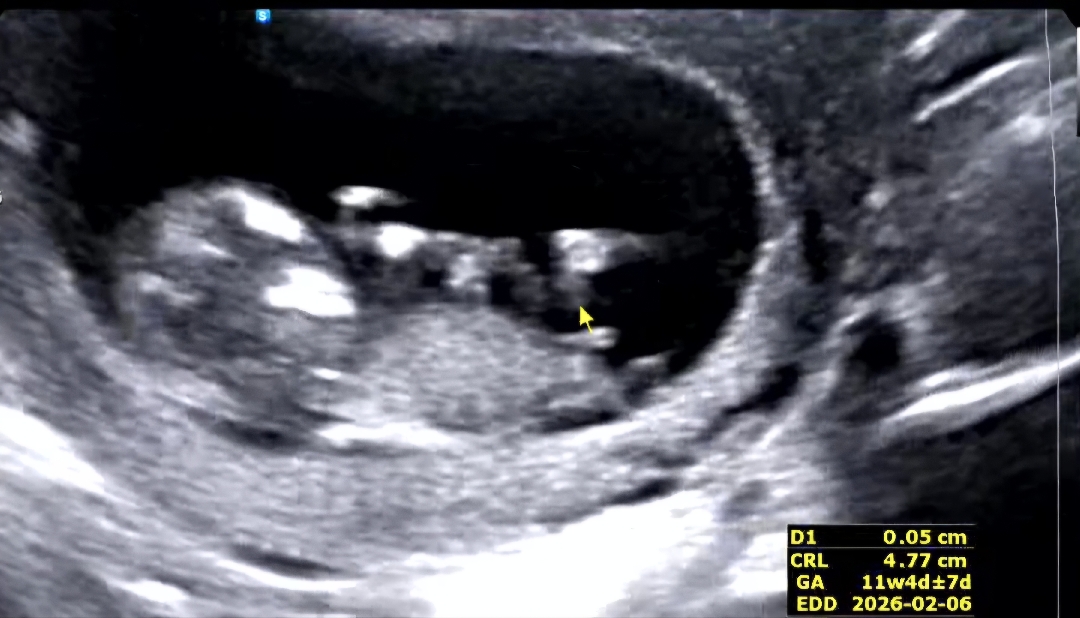

11주2일 성별

아직 많이 이르고 아기가 너무 움직이는바람에 정확한 각도도 없고 ..안보이지만 혹시 요 촘파로 구분이 가능할까요? 혹시나~~해서 올려봅니다 ㅎㅎ 딸일까요 아들일까요 너무 궁금해지네요 ㅎㅎ

저 갈라진 게 생식기 맞다면 딸 같아요!